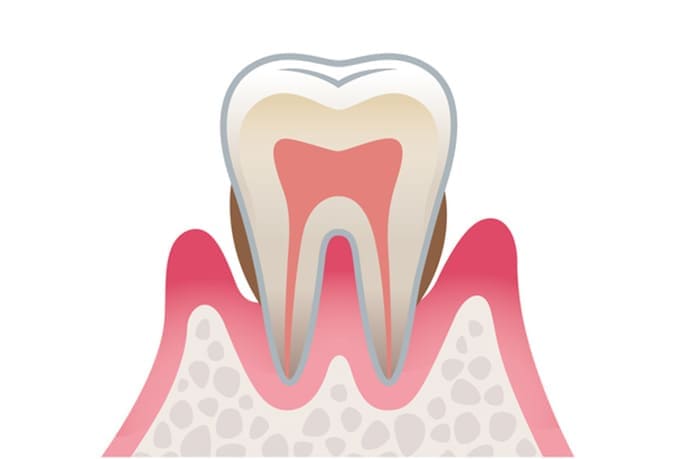

歯周病は、歯周病菌がつくり出す毒素などが原因で歯ぐきに炎症が起こる病気です。

進行すると、歯ぐきの内側にある歯根膜や歯槽骨といった歯を支える組織まで傷つき、放置すると最終的に歯を失うこともあります。

また、近年の研究では、歯肉のダメージ箇所から細菌や炎症物質が体内へ侵入し、全身疾患を引き起こすリスクも指摘されています。当院では、単にお口のトラブルを解決するだけでなく、全身の健康管理という視点から、質の高い歯周病治療とメインテナンスを提供しております。